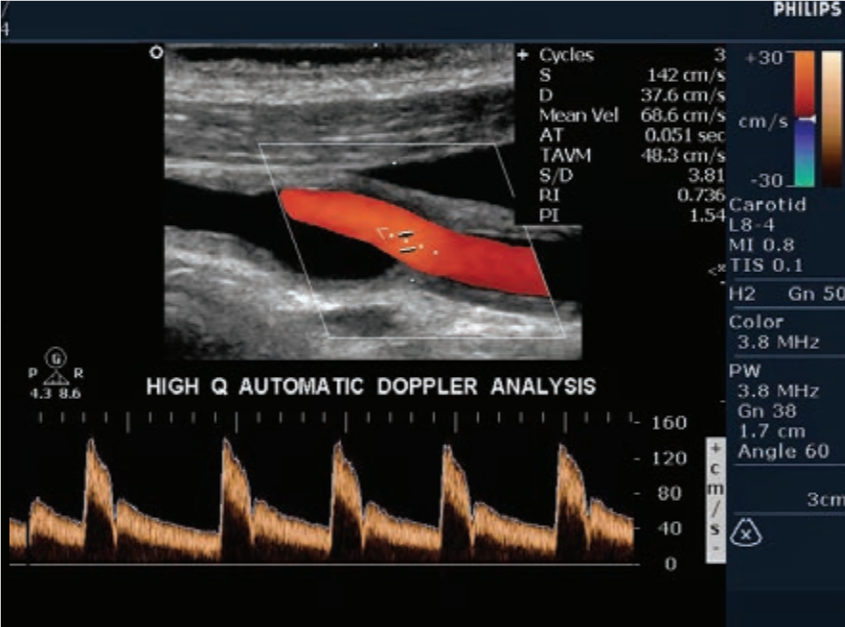

- Gracias a su software de cuantificación QLAB y sus mejoras de configuración específicas de enfermedades cardiovasculares, permite ayudarlo a realizar diagnósticos muchos más rápidos y eficientes.

- El sistema de ecocardiograma iE33 forma parte de la línea de alta gama de ecógrafos Philips.